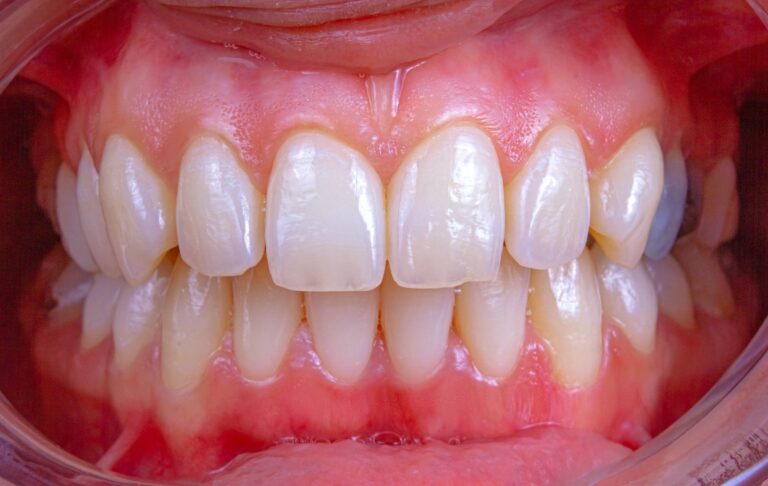

Czym jest bielnica? Bielnica to potoczne określenie zmian o jasnym, białawym zabarwieniu pojawiających się na błonie śluzowej jamy ustnej. Najczęściej termin ten odnosi się do obszarów nadmiernego rogowacenia lub przebarwień, które mogą mieć różne podłoże i wymagać dokładnej diagnostyki stomatologicznej.…